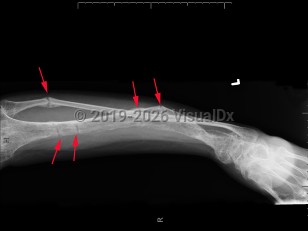

Clinical presentation is variable and typically presents after 18 months of age or when the pediatric patient begins to walk. Symptoms range from growth retardation and short stature to severe rickets or osteomalacia. Some patients have isolated hypophosphatemia detected on serologic testing. The typical presentation is a child with leg bowing and other bone deformities, pseudo-fractures, bone pain, and short stature. Rarely, a patient may present with tetany, dental enamel defects, and spine or pelvic rickets.

Treatment consists of oral phosphate supplementation and calcitriol. Adult patients with familial hypophosphatemic rickets of oncogene origin will usually improve once the tumor causing the disease is removed.